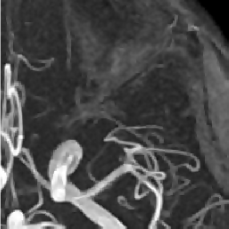

Figure 2: Test Images.

We turn now to test TDIHT for high dimensional signals. We test the performance of several MRI images: the Shepp-Logan phantom, FLAIT brain image, T2 Sagittal view of the lumbar spine and the circle of Willis. The first image is of size 256×256256256256\times 256, while the other are of size 512×512512512512\times 512. They are all presented in Fig. 2.

We focus on the recovery of these images from a few number of Fourier measurements. With 𝛀𝛀{\mathbf{\Omega}} set to be the undecimated Haar transform with one level of resolution (redundancy four) and 𝐃𝐃\mathbf{D} its inverse transform, we succeed to recover the phantom image using only 181818 sampled radial lines, which is only 6.5%percent6.56.5\% of the measurements. This number is only slightly larger than the number needed for GAP, relaxed ASP (RASP) and Relaxed ACoSaMP (RACoSaMP) in [10, 38]. The advantage of TDIHT over these methods is its low complexity as it requires applying only 𝐌𝐌{\mathbf{M}} and its conjugate and 𝛀𝛀{\mathbf{\Omega}} and its inverse transform while in the other algorithms a high dimensional least squares minimization problem should be solved. Note also that for AIHT and RAHTP the number of radial lines needed for recovery is 353535 and for IHT (with the decimated Haar operator with one level of resolution) we need more than 505050 radial lines.